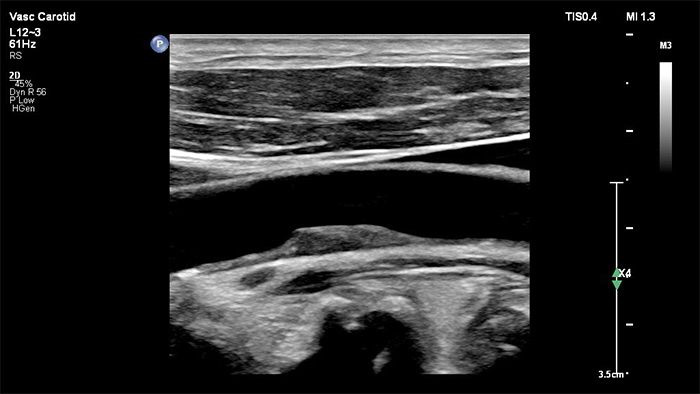

Der XL14-3 xMATRIX Schallkopf verfügt zudem über xPlane Doppler-Funktionen. Im xPlane PW-Doppler-Betrieb lässt sich das Doppler-Probenvolumen anhand der Referenzbilder in der Längs- und Querebene präzise platzieren. Wichtigster Vorteil: xPlane Doppler reduziert Platzierungsfehler bei Probenvolumen und führt bei der Untersuchung grösserer Stenosen zu einer besseren Reproduzierbarkeit und Konstanz.